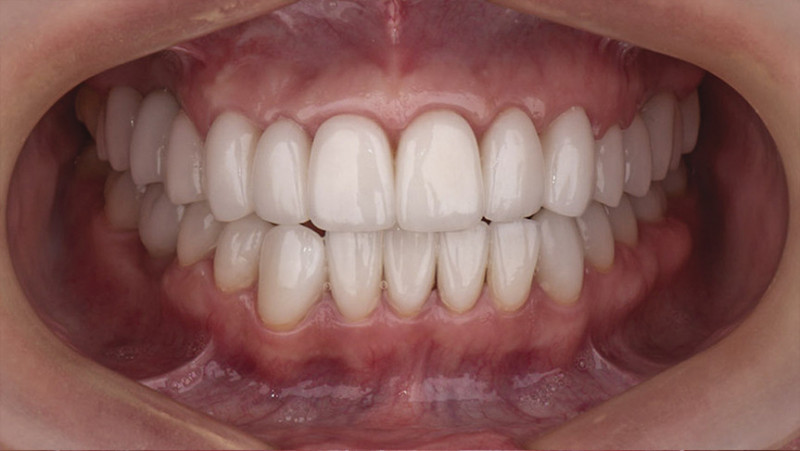

Установка керамической коронки

Все зубы покрыли керамическими винирами и коронками. Установили коронки на имплантаты.